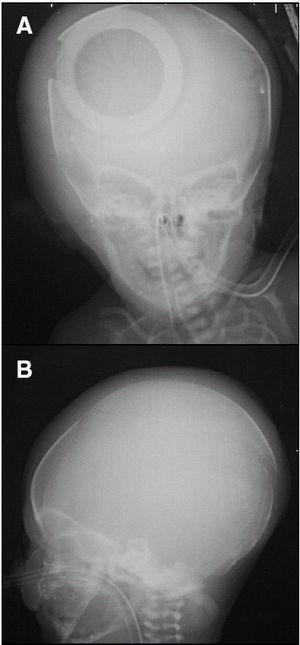

Fruto de esa cesárea nace un varón de 2.000 g, con Apgar a 1 min 0. Se inicia reanimación según protocolo, requiriendo de forma progresiva ventilación con O2 a presión positiva en bolsa autoinflable, intubación endotraqueal, masaje cardíaco, adrenalina endotraqueal, canalización de vena umbilical, adrenalina, líquidos y bicarbonato intravenosos. Finalmente, a los 10 min de reanimación se consigue una frecuencia cardíaca mantenida en torno a 100 lat./min y unos pulsos periféricos palpables, aunque débiles. Se traslada a UCIN en incubadora de transporte conectado a ventilación mecánica. En la exploración física a su ingreso en UCIN destaca un mal estado general, mala coloración, fractura craneal (parietoocciptital) derecha con importante edema de partes blandas y despegamiento del pabellón auricular derecho (fig. 1). Resto de exploración normal. Las constantes vitales al ingreso: Frecuencia cardíaca 154 lat./min, frecuencia respiratoria 45 resp./min (SIMV), PA 27/23/18, SatO2 80 % con FiO2 100 %. Gasometría al ingreso (venosa): pH 6,57, pCO2 102, pO2 28,8, Bic 4,5, EB 23, lactato 16. Analítica al ingreso: Hb 10,7, Hto 31,8, leucocitos 10.700 (fórmula normal), urea 19, creatinina 1,01, CK 868 U/l (CK-MB 14,6 ng/ml), Na 136 mEq/l y K 8,06 mEq/l. Se practica radiografía simple de tórax, apreciándose pulmón blanco, por lo que se administra surfactante pulmonar, con adecuada respuesta, permitiendo disminuir FiO2 hasta 40 %. La ecografía transfontanelar al ingreso objetivó signos de edema cerebral, sin hemorragia. Se pautaron expansores de volumen, bicarbonato, transfusión de hemoderivados (concentrado de hematíes y plasma) y se inició perfusión de adrenalina intravenosa a 1 μg/kg/min, pese a lo cual no remontó tensiones. Se pautó hidrocortisona, sin respuesta. Control ecográfico posterior (7 h de vida): aumento de la ecogenicidad con pérdida de la ecoestructura normal en hemisferio cerebral derecho, compatible con hemorragia parenquimatosa cerebral. La hemorragia condiciona cierto efecto masa con signos de herniación subfalciana. El paciente falleció a las 8 h de vida.

Figura 1. Radiografía anteroposterior (A) y lateral (B) de cráneo donde se observa fractura parietooccipital derecha (óbviese artefacto de incubadora).